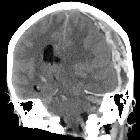

Duret hemorrhage is a small hemorrhage (or multiple hemorrhages) seen in the medulla or pons of patients who are rapidly developing brain herniation, especially central herniation.

Raised supratentorial pressure causes the brainstem and mesial temporal lobes to be forced downwards through the tentorial hiatus. As a result of this shift, it is believed that perforating branches from the basilar artery and/or draining veins are damaged with resultant parenchymal hemorrhage. Most commonly it is seen in patients with severe herniation 12 to 24 hours prior to death .

The classical appearance of a Duret hemorrhage is a single small, round hemorrhage located in the midline of the medulla or pons near the pontomesencephalic junction. Often, however, these hemorrhages can be multiple or even extend into the cerebellar peduncles.